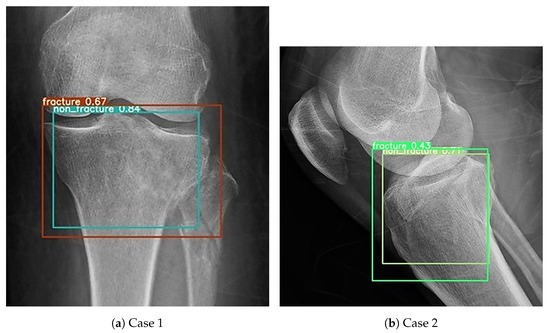

In addition to standardized lateral cephalometric radiographs, comprehensive assessment using dental cone-beam computed tomography (CBCT) and CT has become commonplace in the diagnosis and treatment of jaw deformities. Simulation based on cephalometr...